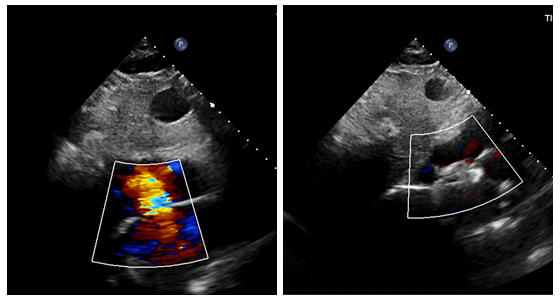

患者手术前后超声对比图

手术在局部麻醉下进行,患者全程保持清醒,生命体征平稳。刘茂林主治医师主刀,经股静脉建立微创通道,术中不依赖DSA血管造影、不使用造影剂、无需放置经食管超声探头,仅依靠单纯TTE实时超声影像完成缺损定位、封堵器测量、植入与释放。术中超声屏幕清晰显示,封堵器放置位置理想,无残余分流,手术效果达到预期。整个过程无X线辐射暴露,患者无任何不适感,真正实现了绿色、微创、安全的手术目标。